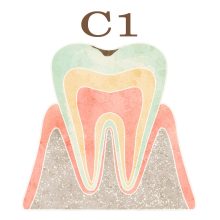

「C」とは歯科検診でよく使われる記号で、”caries”(カリエス、つまり虫歯)の頭文字を表します。「C」の後につくアルファベット(O)や数字(1,2,3,4)は、虫歯の進行具合を示します。

・C1(シーワン): 歯の表面にあるエナメル質に発生した虫歯の段階を指します。エナメル質内にできた虫歯は痛みやしみることがないため、気付きにくい場合があります。しかし、放置しておくと虫歯が象牙質(歯の内部組織)に達し、進行してしまう可能性があります。そのため、早期に治療することが重要です。